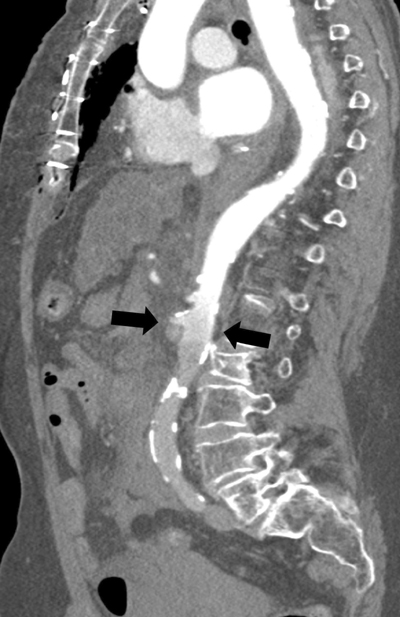

Figure 4

Parasagittal reformatted image of the watershed zone (black arrows) at the level of the superior mesenteric artery (SMA).

In this case, no luminal contrast opacification nor active haemorrhage distal to the SMA was present due to the watershed phenomenon, with the blurred area at the level of the SMA and despite the haemorrhage surrounding the right superficial femoral artery.

Since distal to the SMA no vascular enhancement was obtainable, active bleeding could not be ruled out. Awareness of the watershed phenomenon is crucial, since artefacts can be mistaken for pseudolesions such as thrombus, dissection, or vascular occlusion. The watershed area can also potentially obscure true pathology [2], with potentially fatal consequences, as in this case where an active bleeding could be overlooked.